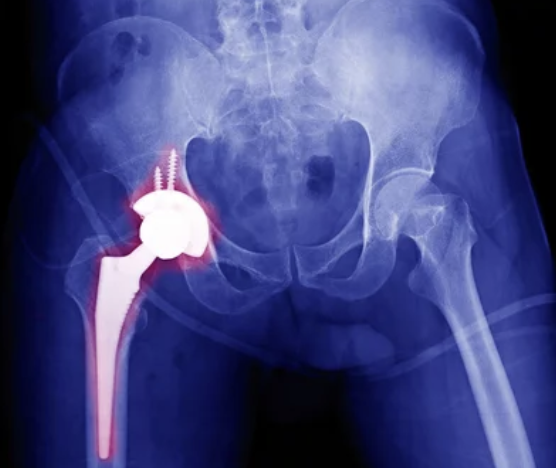

고관절 통증의 진단과 치료는 의사의 전문적인 평가와 조언이 필요합니다. 의사는 환자의 증상을 평가하고 필요에 따라 신체 검사나 영상 검사를 통해 진단을 내릴 수 있습니다. 관절염 등의 염증성 질환인 경우 항염증 약물이나 생활습관의 변화를 통한 관리가 필요합니다. 골관절탈구나 심한 손상의 경우 수술이 필요할 수 있습니다. 물리치료나 침술 등의 보조 요법도 통증을 완화하는 데 도움이 될 수 있습니다.